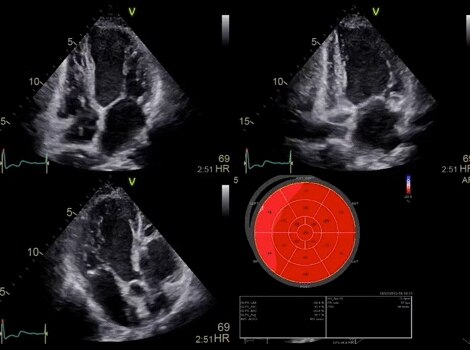

Vivid Portfolio

Cardiac Auto Doppler automatically provides Doppler measurement results for the most common parameters, with minimal user guidance.  Read More

Vivid E95

cSound beamforming technology for exceptional visualization quality with impressive resolution in 2D, color flow, Doppler and 4D formats. Read More

Provides instant access to predefined (factory or user created) 4D views during live mode to potentially provide more consistent data while reducing scanning time. Read More

VividTM Family Cardiac Ultrasound Automated Function Imaging (AFI)

Assess left ventricular function and cardiac performance with clarity, improving clinical confidence.  Read More

Vivid Family Cardiac Ultrasound

Vivid E95 with cSound performance makes 4D as easy as 2D to quantify left ventricular wall motion. Read More

Vivid™ Family Cardiac Ultrasound Automated Function Imaging (AFI)

Automated Ejection Fraction and LV wall motion quantification. Read More

Semi-automated 3D valve assessment. Read More

Vivid 4D

4D acquisition, navigation and quantification to enhance procedure planning. Read More

Provides Doppler measurement results for the most common parameters, with minimal guidance. Read More

Vivid Family Ultrasound

Vivid Family Cardiac Ultrasound with Auto EF